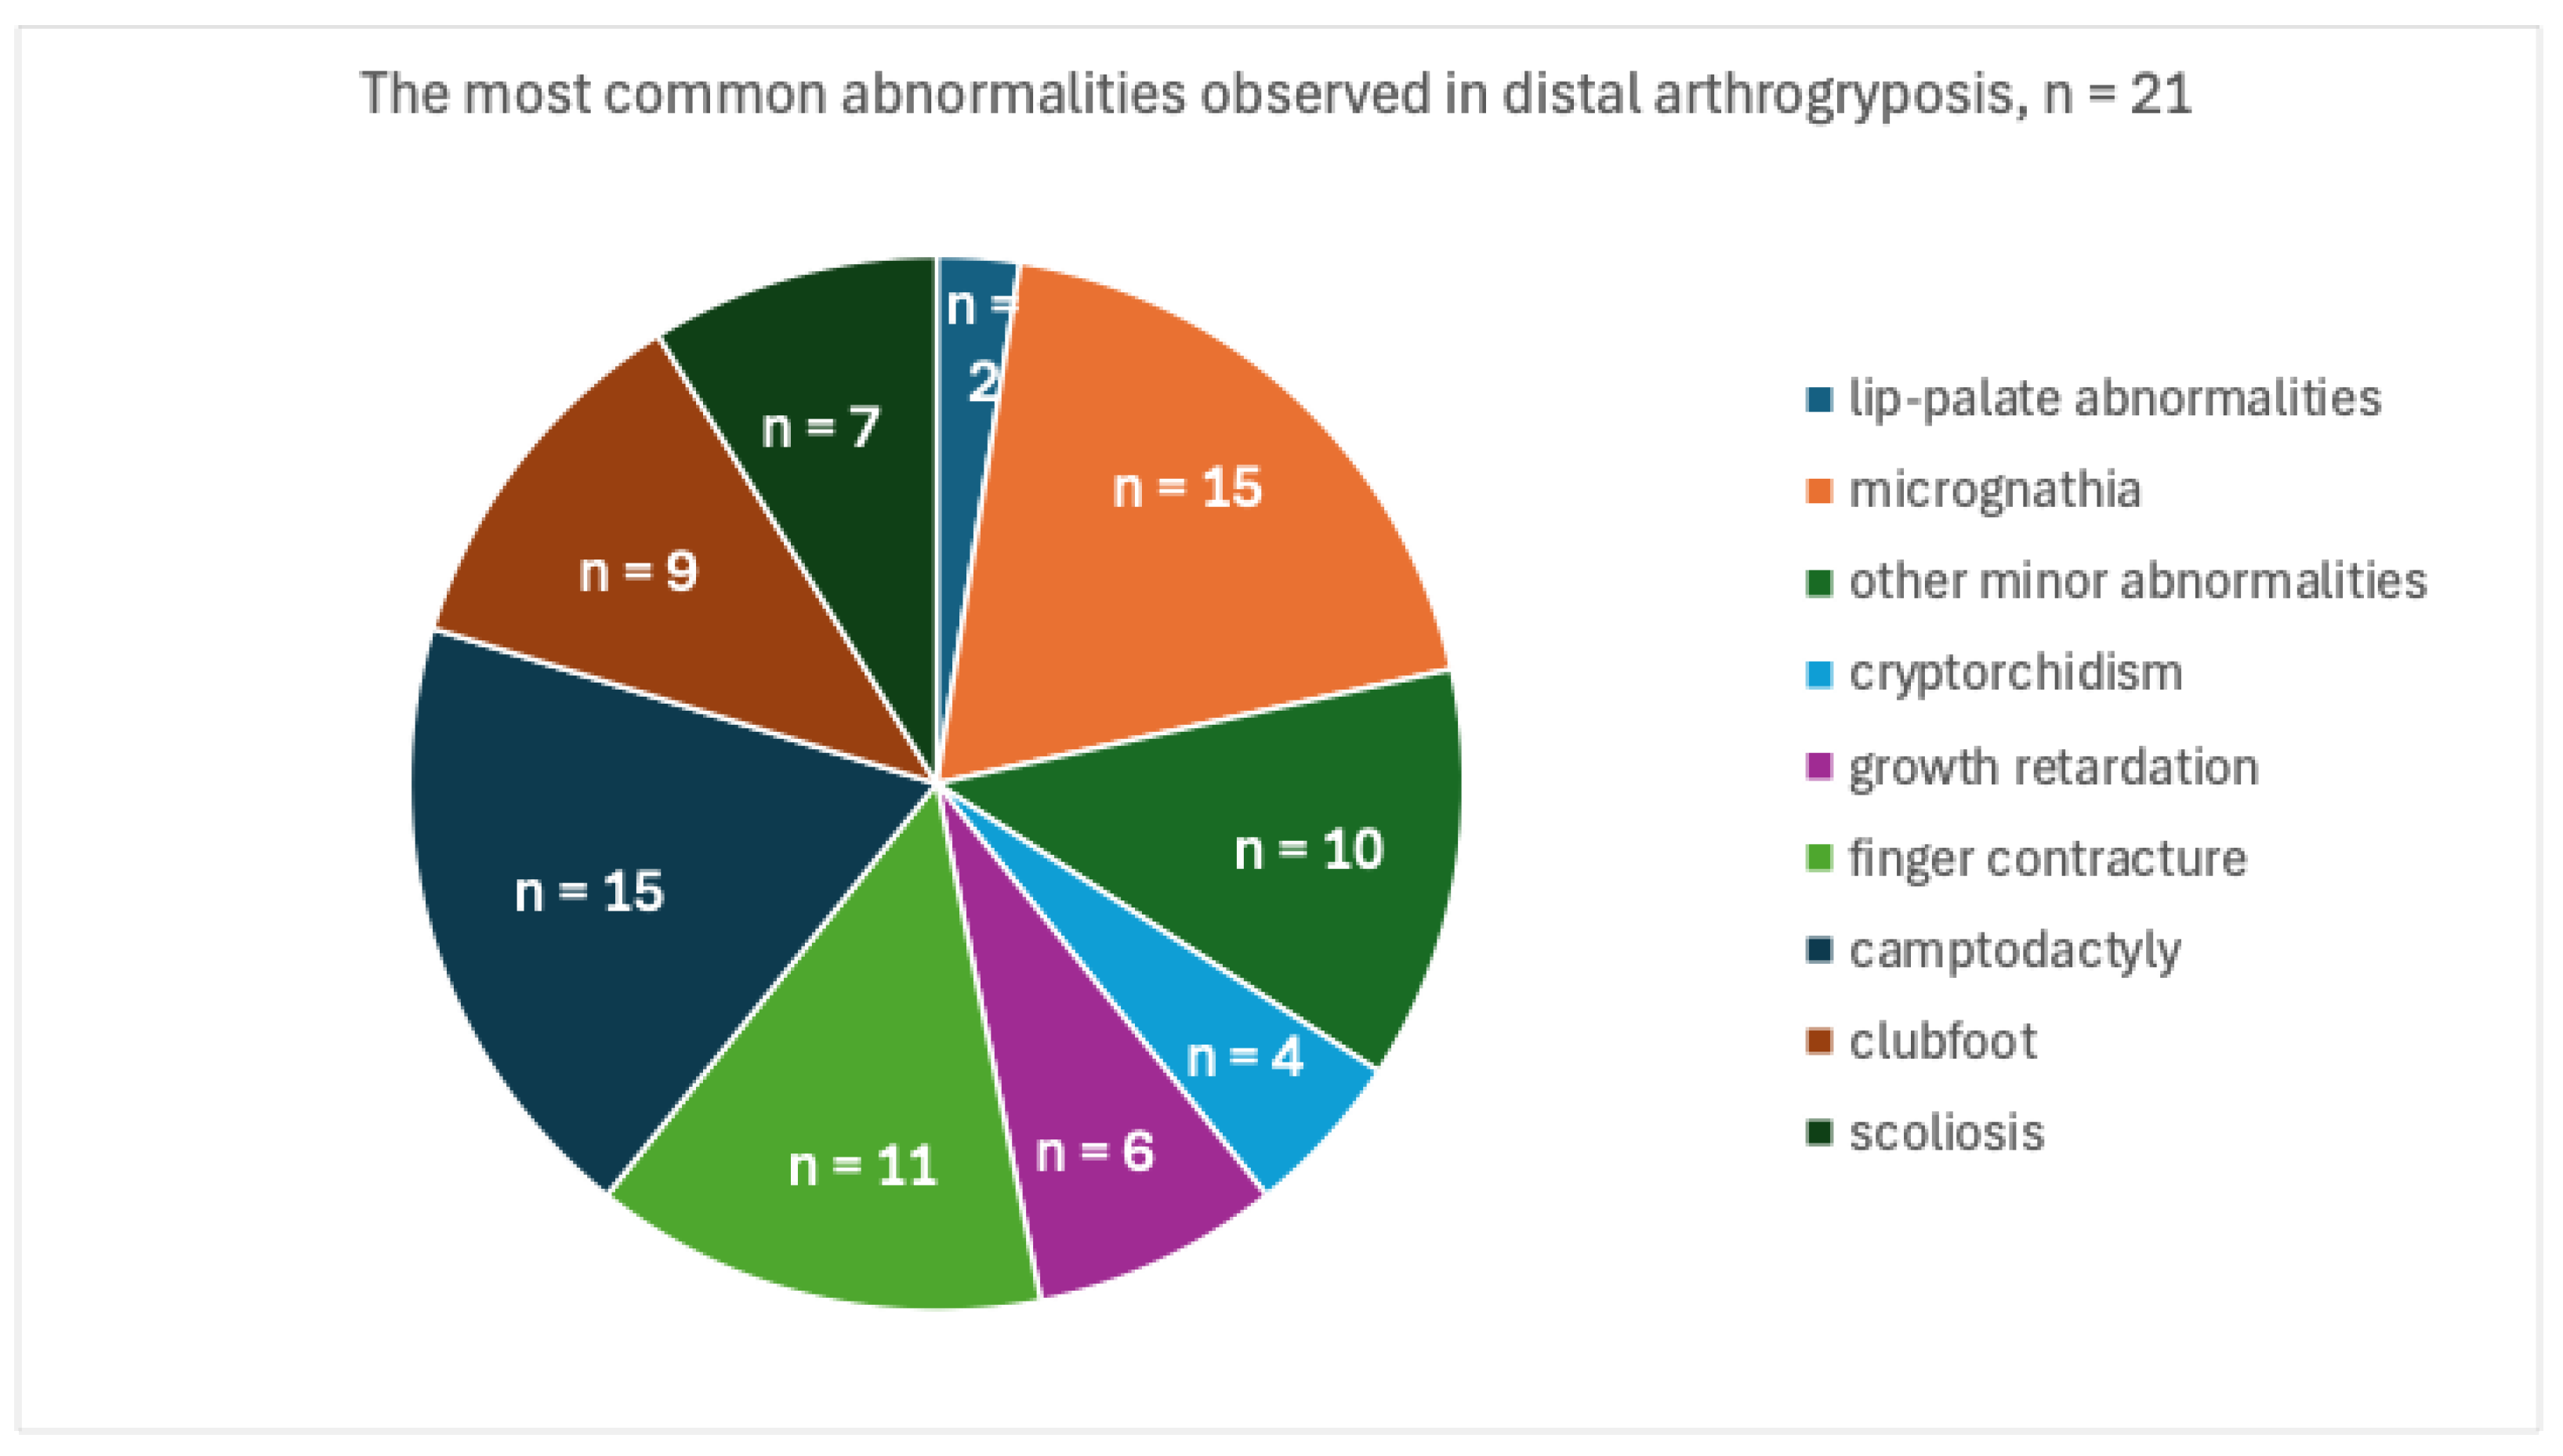

3. Results

Case Report

4. Discussion and Conclusions